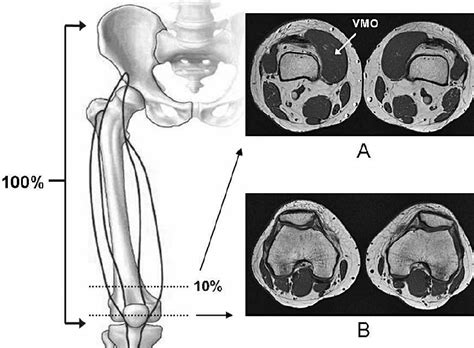

The quads consist of four muscles, shown below: A chiseled vmo muscle is an unmistakable mark of the fittest, most dedicated cyclists. If you have a tracking issue. The vmo is the most medial of your quadriceps muscles, and one often blamed for knee issues like patellar tracking disorder and patellofemoral pain syndrome (pfps). Vastus medialis is one of the four muscles that make up the quadriceps group of muscles. The vastus medialis oblique (vmo) portion on the muscle has an extra function of helping to control how the kneecap moves and provides stability. Atrophy of the vmo, imbalance of the vmo/vastus lateralis (vl) strength, and altered neuromuscular timing of the different parts of the quadriceps muscle have all been described in patellofemoral pain. Here you may to know how to train vmo muscle. It originates from the upper part of the femoral shaft and inserts as a flattened tendon into the quadriceps femoris tendon. The vastus medialis is a muscle present in the anterior compartment of thigh. The vmo muscle is the vastus medialis oblique muscle in the thigh. Vmo muscle & meniscus health. Strengthening this muscle is particularly important for knee.

This group is located on the front of your thigh. It is important for knee rehabilitation. The vastus medialis (vastus internus or teardrop muscle) is an extensor muscle located medially in the thigh that extends the knee. A big, strong vmo is associated with bodybuilders who desire defined, sculpted quads. Open kinetic chain (okc) studies suggested that the optimum ratio of vmo:vl is.

A chiseled vmo muscle is an unmistakable mark of the fittest, most dedicated cyclists. If you're an athlete, your vmo doesn't need to look like it's bursting through your skin. The vastus medialis muscle is a part of the quadriceps muscle group. The vastus medialis is part of the quadriceps muscle group. Vastus medialis is one of the four muscles that make up the quadriceps group of muscles. Vastus medialis oblique (vmo) and vastus lateralis (vl) are two key muscles that help maintain patellar alignment. Vastus medialis (vm) on the inside of the thigh. The vastus medialis oblique (vmo) portion on the muscle has an extra function of helping to control how the kneecap moves and provides stability.